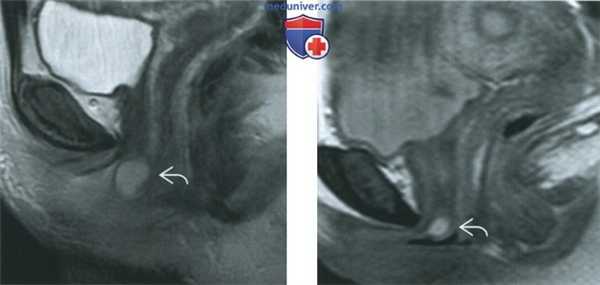

(Слева) При МРТ на Т2-ВИ в сагиттальной плоскости определяются классические признаки кисты железы Скина (парауретральной железы). Причиной образования таких кист бывает закупорка выводного протока и последующее расширение самой железы.

(Справа) При МРТ на Т2-ВИ в сагиттальной плоскости у другой пациентки визуализируется маленькая гиперинтенсивная киста, расположенная у наружного отверстия уретры, - признаки, характерные для кисты железы Скина.